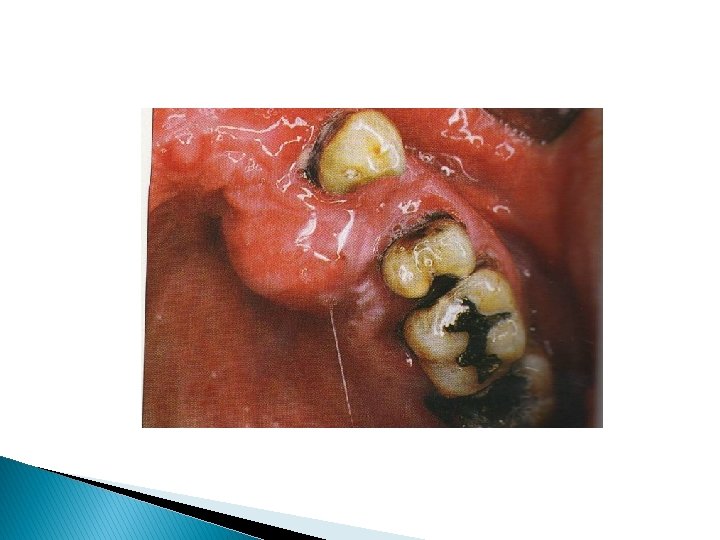

Étude clinique Ostéites de causes exogènes Ostéites liées aux bisphonates -asymptomatique pdt plusieurs semaines voire des mois. -exposition osseuse -plus ou moins douloureuse -sans tendance à la guérison spontanée -os blanc ou grisâtre -muqueuse oedématiée, érythémateuse ou ulcérée -suppurée ou non -mobilité dentaire -hypoesthésie

Ostéonécrose sous bisphonates